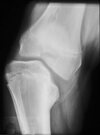

obese 3 y/o w/ unilateral bowing (30 deg) seen in image, what's the appropriate managment?

**infantile tibia vara (Blount's disease). ** The radiograph shows severe deformity with the characteristic Langenskiold stage 3 changes of the medial proximal tibial metaphysis that distinguish it from physiologic bowing. * **proximal tibiofibular osteotomy with acute correction into slight valgus** to unload the damaged area of the physis. This method provides the best results in patients younger than age 4 years. * Continued observation would result in progressive deformity. Bracing is most effective in younger children with less severe deformity. Lateral proximal tibial hemiepiphysiodesis relies on growth of the injured medial physis for correction and would result in severe tibial shortening in this young child. Complete epiphysiodesis also produces severe shortening and requires multiple lengthening procedures